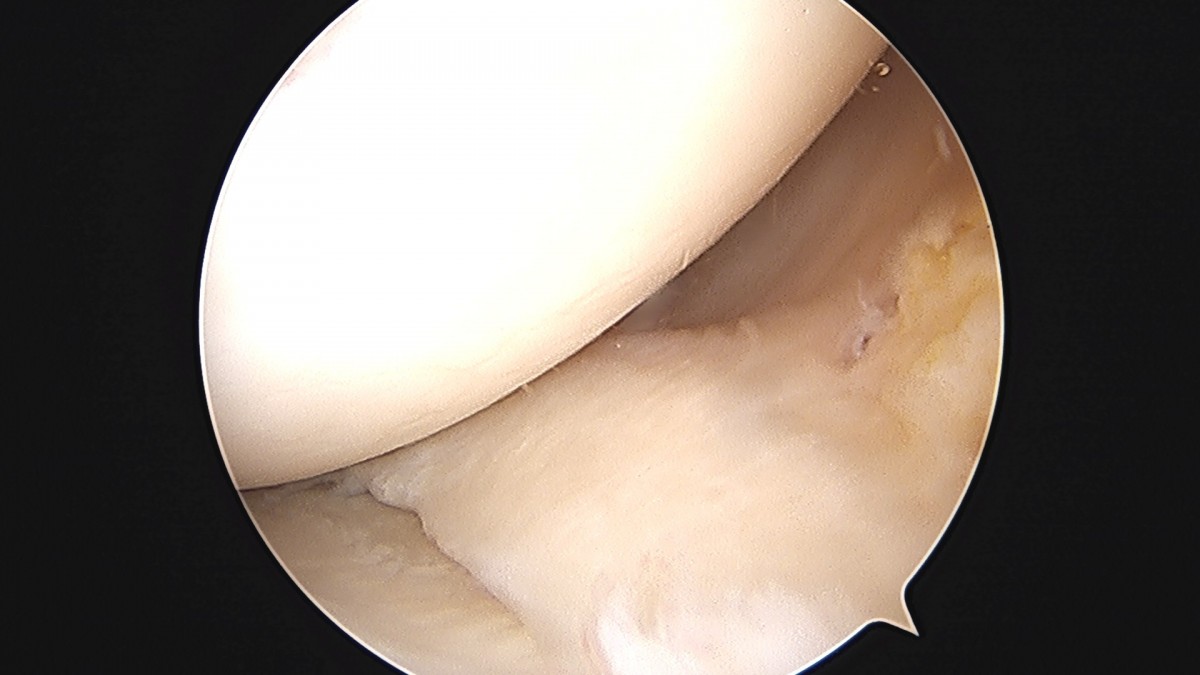

이재상원장님 무릎 반월상 연골판 절제술 강일O 환자

작성자 최고관리자 댓글 0건 조회 372회 작성일 25-09-16 16:12